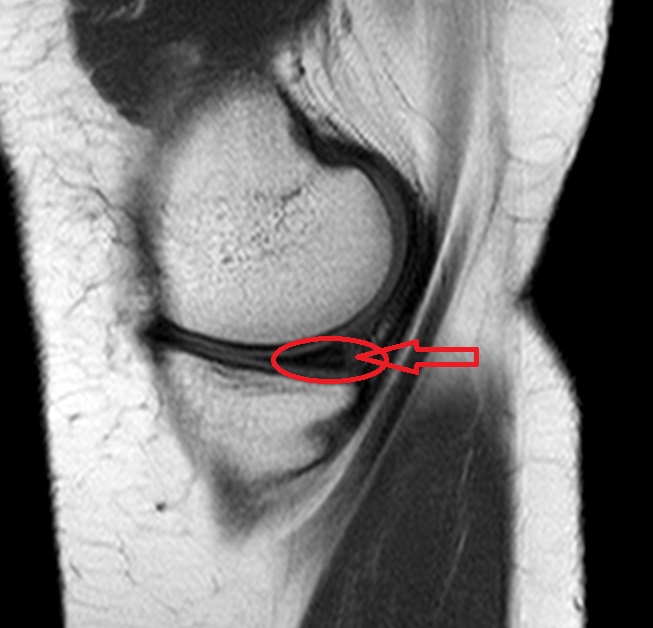

Kommt es nun zu einem Meniskusschaden oder Meniskusriss kann eine Operation notwendig werden. Bereits ab dem ersten Tag nach einer Meniskusteilresektion kann Ulla Thiel eine Belastung des Knies erfolgen. Bei kaputtem Meniskus wird zu oft operiert.

Bei Meniskusrissen bringt ein chirurgischer Eingriff oft keine Vorteile zeigen Studien. Kein Erguss entstanden ist und. Ein Meniskusriss ist einer der häufigsten Gründe für operative Eingriffe in Deutschland.